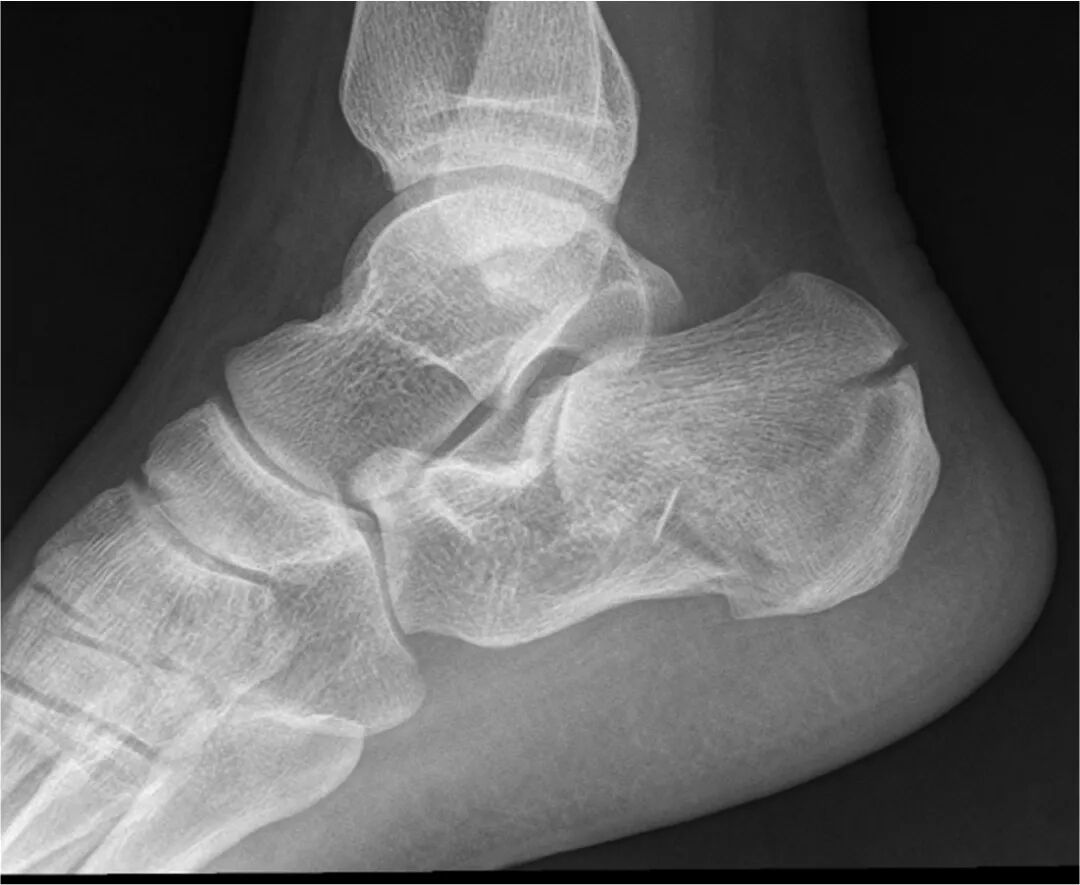

距骨外側突起骨折(捻挫による骨折) 足関節の捻挫だと思っていて、腫脹や痛みが強い場合、骨折を疑いますが、 足関節内の稀な骨折の一つに、「距骨外側突起骨折」があります。 この骨折は、スノーボードの外傷として増えつつあると言われています。 このページでは、実際の患者さんの例もご紹介して、 距骨外側突起骨折とはどんな外傷であるのかをご説明たいていのケースでは、腫脹や痛みが緩和されて、後遺障害が残らずに治癒します。 剥離骨折に至った場合、治療は 4 ~ 6 週間程度のギプス固定が基本ですが、骨片が大きいケースでは、外科手術(固定術)を選択します。反対に、足関節が強く外転した場合には、外果は距骨に突き上げられて骨折し、内果は剥離骨折を起こすことがあります(外転骨折)。 足関節の図・説明(weblio辞書) 足関節果部骨折の説明(日本整形外科学会) 2足関節の骨折(足関節果部骨折)の治療

骨折が見過ごされると、「難治性の捻挫」として長期加療されることがある 4 .治療方法距骨骨折の治療 ここでは,MartiWeberの分類に準じて,各 骨折型の治療原則を述べる 1距骨辺操部の距骨骨折 (1)ー剥離骨折"は,距骨頚部の前外上面に多く, ほとんどの場合,吸収されるPTBギプスで 3週間固定後,自動運動を中心とした後療法足背動脈の拍動を確認して下腿から足尖部までギプス a 距骨下関節の解剖および脱臼の発生機転について 固定を施行した。術後のレ線像で腓骨の剥離骨折を認 距骨は4個の骨と接している。すなわち内側上方は めている。

足関節外果剥離骨折を伴った距骨外側突起骨折の一例 三島 香織 , 池田 聡 , 有田 忍 , 田中 伸哉 整形外科と災害外科 56(1), , 0711/19/ · 距骨下関節症(距骨下関節炎)はどういう状態? 距骨下関節において、炎症が起こり、変形がでているものです。 なぜ、距骨下関節に炎症や変形が起こるのか?という疑問が生じますよね。 初めのきっかけは かかとの骨折 であることが多いです。Article "前距腓靱帯の距骨付着部剥離骨折の1例" Detailed information of the JGLOBAL is a service based on the concept of Linking, Expanding, and Sparking, linking science and technology information which hitherto stood alone to support the generation of ideas By linking the information entered, we provide opportunities to make unexpected discoveries and obtain knowledge

距骨骨折の症状 診断 治療 骨 筋肉 関節の病気 All About